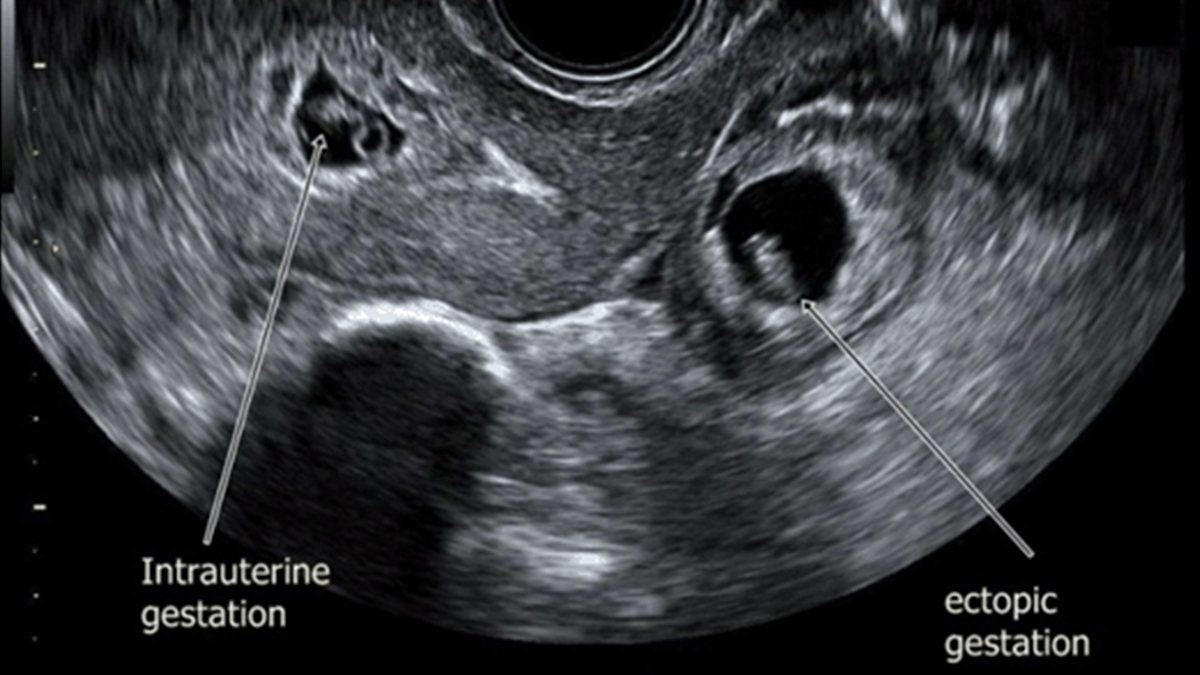

Heterotopik gebelik, ayrı implantasyon bölgelerine sahip iki eş zamanlı gebeliğin varlığına işaret eder. Heterotopik gebeliklerde bir fetüs olması gereken yere, yani rahme yerleşirken diğeri rahim dışına, genellikle de fallop tüplerine yerleşir. Tüp bebek gibi yardımcı üreme teknikleriyle gebelik elde eden kadınlarda daha sık görülebilen heterotopik gebeliğin doğal yollarla hamile kalanlarda görülme olasılığı ise 30.000 ila 70.000’de 1’dir.

2. Ultrason Muayenesi Olun

Heterotopik gebelik teşhisi ultrason muayenesi ile konabilir. Ancak doktorlar, rahimde gelişmekte olan fetüse odaklanacağından ultrason muayenesinde heterotopik gebeliği gözden kaçırmaları olasıdır. Heterotopik gebelikten şüpheleniliyorsa şayet dördüncü veya beşinci haftada ultrason muayenesi ile teşhis doğrulanabilir veya elenebilir.